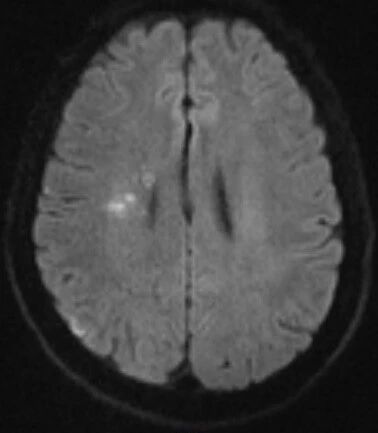

辅助检查:头颅MRI+MRA提示急性多发梗塞灶,右侧颈内动脉未见显影。

MRA示右侧颈内动脉未见显影

右侧大脑半球、基底节区多发梗塞灶

(急性期)